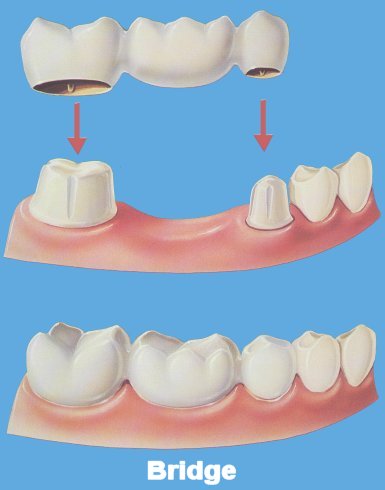

Dental bridges perform similarly to "real 'bridges', as in they 'bridge the gap' created by missing teeth.

Dental bridges perform similarly to "real 'bridges', as in they 'bridge the gap' created by missing teeth.